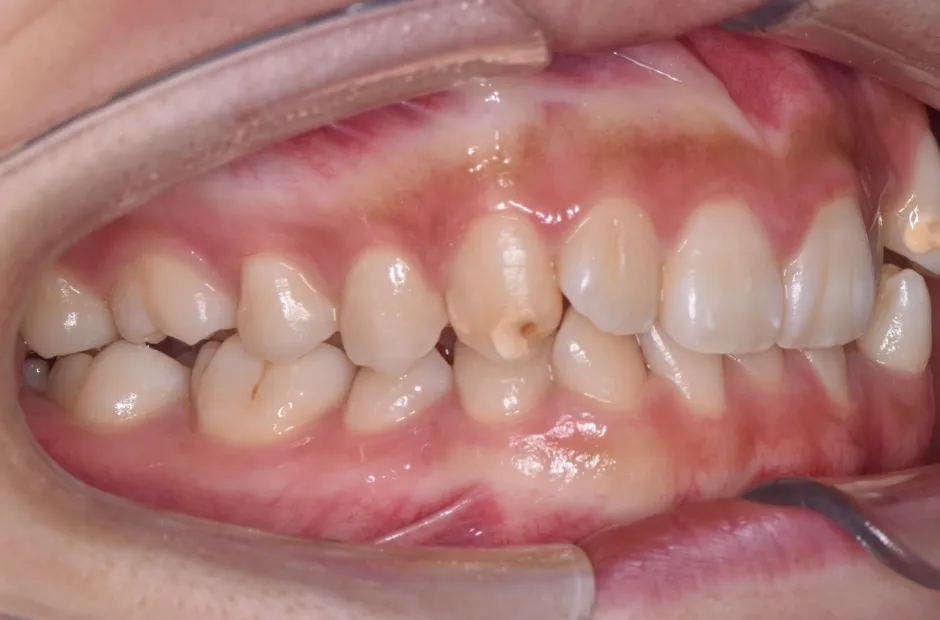

八重歯・でこぼこ・乱ぐい歯

(叢生)

歯が並ぶスペースが足りないために、歯が重なったり前後にずれて生えていたりする状態です。犬歯(八重歯)など目立つ部分の歯列が乱れている場合は、口元の印象に悪影響を与えます。原因としては、遺伝や乳歯の早期抜歯、顎の成長不足などがあげられます。歯磨きが不十分になりやすく、虫歯や歯周病のリスクが高まりやすい不正咬合です。矯正治療を受けると、見た目がよくなるだけでなく清掃性が高まり、お口の健康を維持しやすくなります。

| 診断名・主訴 | 下顎前突、叢生 |

|---|---|

| 年齢・性別 | 23歳・女性 |

| 治療期間・回数 | 3年 |

| 治療に用いた主な装置 | 上顎5,5 下顎4,4 |

| 抜歯部位 | 舌側矯正 |

| 治療費 | 100万円(税抜) |

| リスク・副作用 | 装置による違和感・疼痛・歯肉退縮・歯根吸収・虫歯のリスクなど |